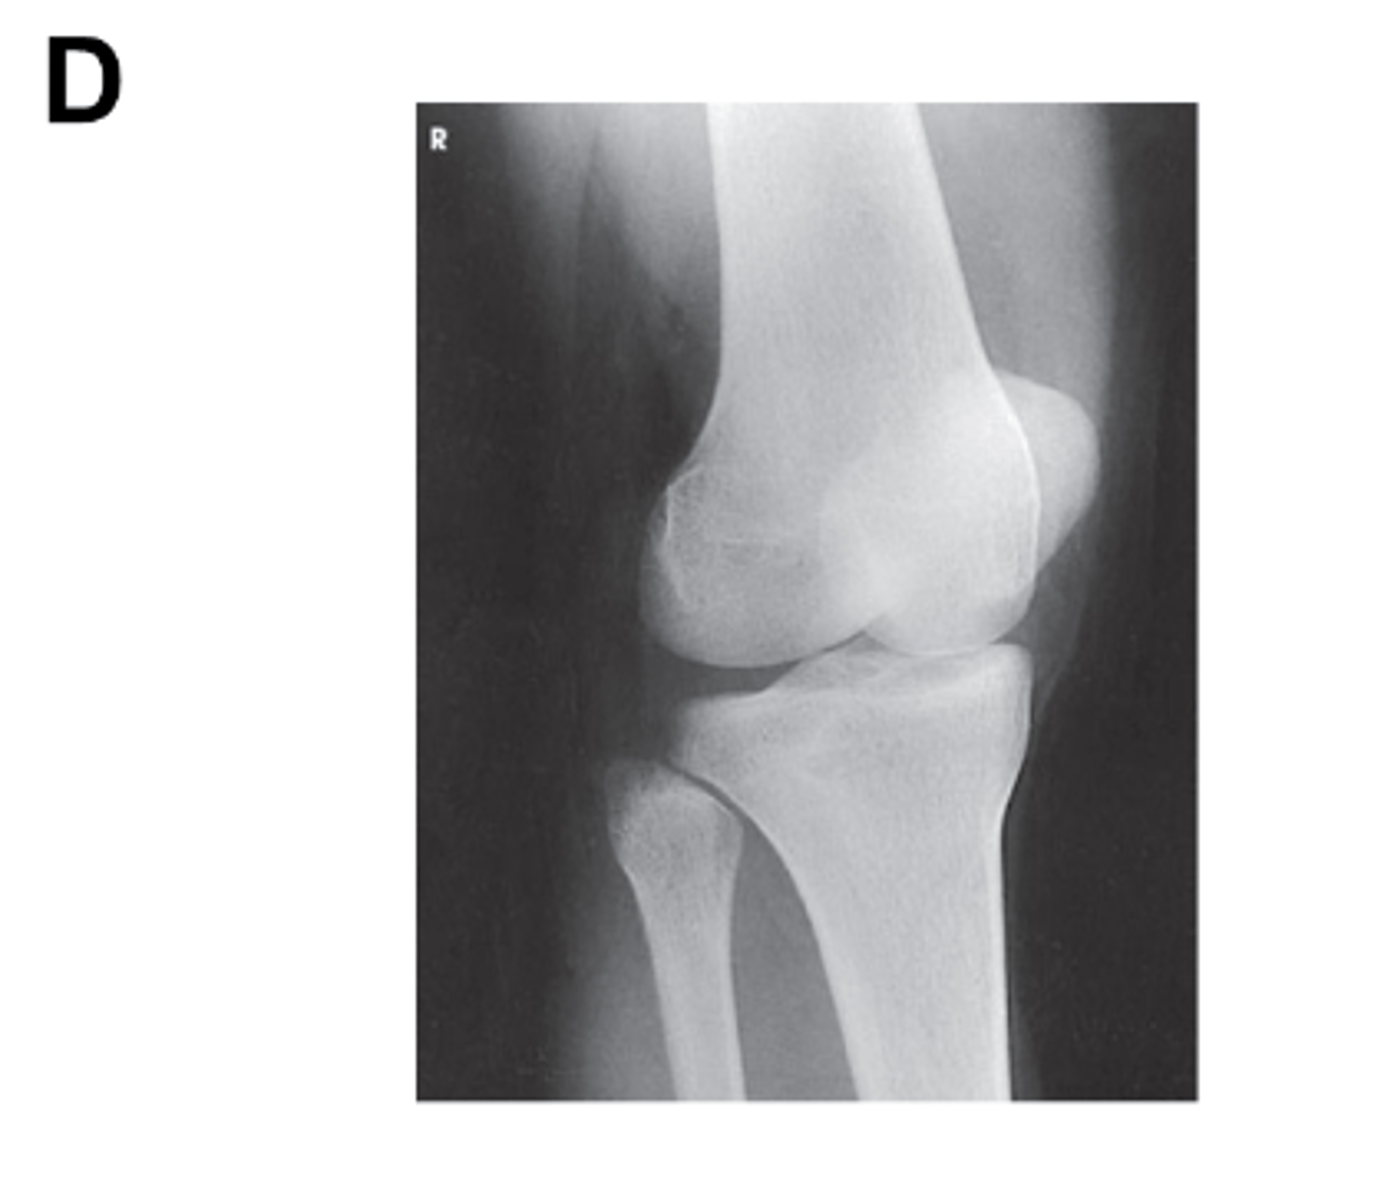

Identify the projection. (Be prepared to critique for positioning on the quiz)

AP Oblique Knee, medial rotation

Is there an angle on the CR in this projection? (Be prepared to explain how you know on the quiz)

Yes